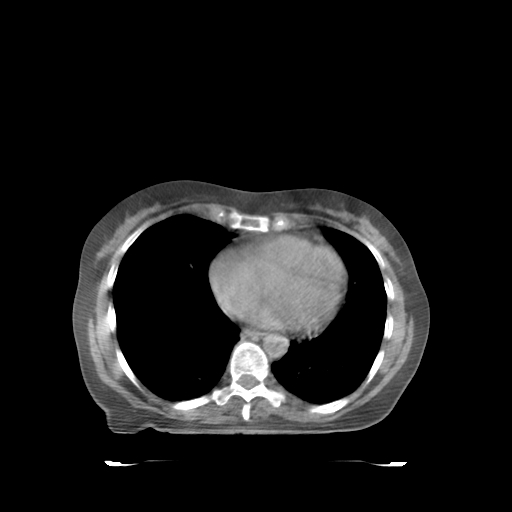

ClearRT® Images

Imaging Information

ClearRT®

Protocol

thorax-medium-FOV44 cm

Scan Length

23 cm

KVCT Imaging Time

24 sec